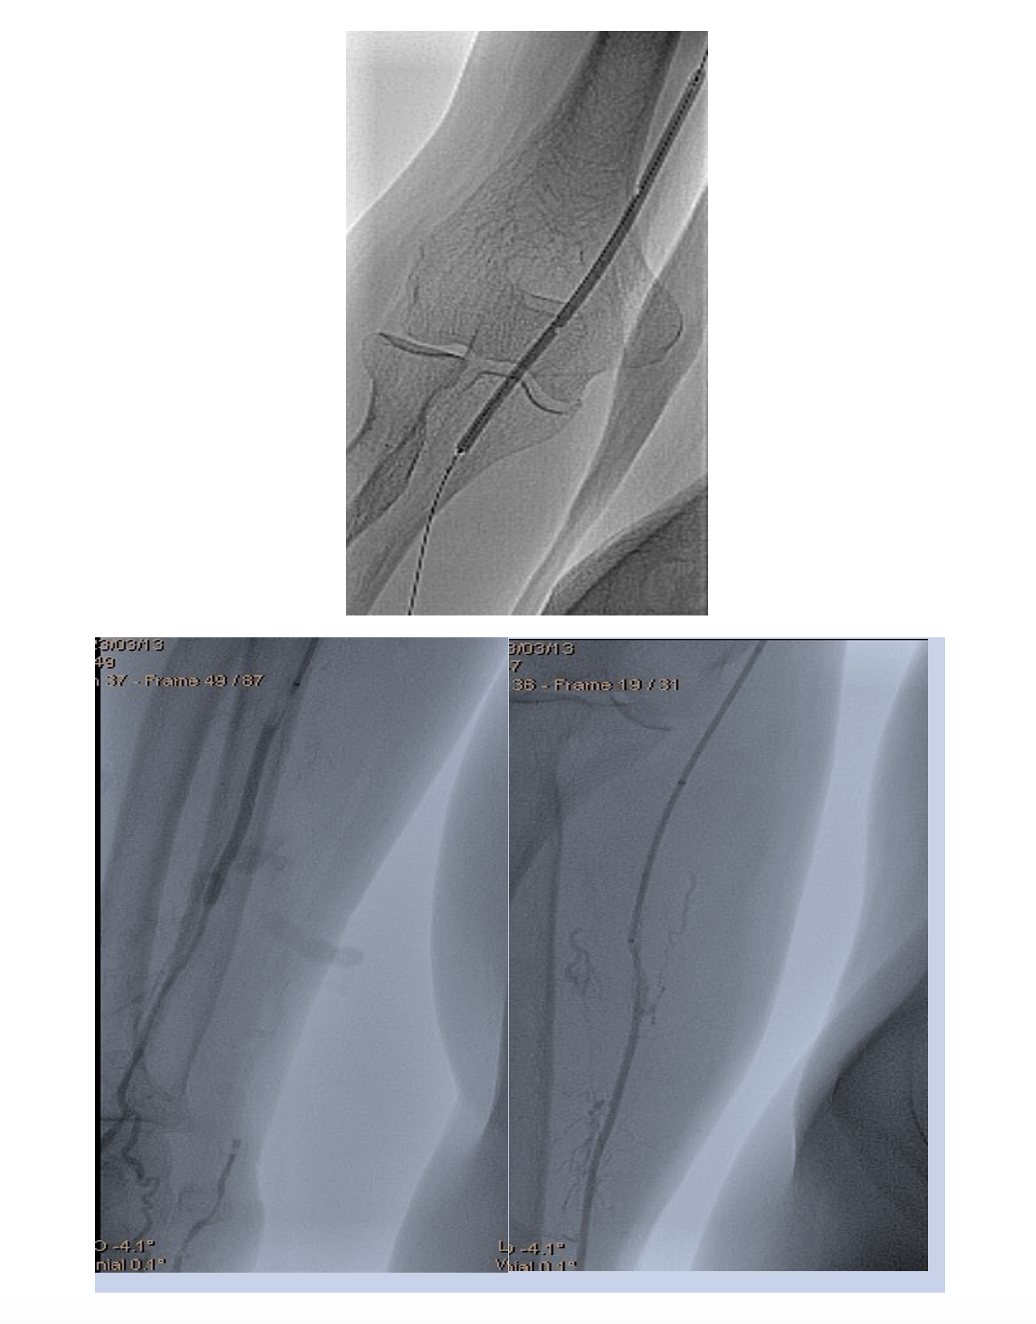

The same introducer was redirected with the tip in the right common femoral artery. PTA of the right SFA, PFA, and popliteal and posterior tibial arteries was performed. Recanalization with a 0.035" Stiff Glidewire (Terumo) and a NaviCross Support Catheter (Terumo). The “riding” thrombus at the SFA/PFA bifurcation then migrated distally and occluded the SFA and PFA (Figure 8). We began EVT from the proximal segment of the SFA, with the same 2.06 mm AngioJet Solent Omni catheter. EVT was performed in the middle segment of the SFA and the popliteal artery (Figure 9). Due to residual thrombosis in the distal segment of the SFA, a balloon dilatation with a 5/120 mm Armada catheter (Abbott) was done (Figure 10).

Thereafter, the right PFA was recanalized with a 0.035" Angulated Glidewire (Terumo) and again EVT was performed with the 2.06 mm AngioJet Solent Omni (Figure 11).

Balloon dilatations in the posterior tibial and tibiofibular trunk were done with 2/120 mm and 3/120 mm Pacific Plus balloons (Medtronic). Because of persistent thrombosis in the proximal segment of the posterior tibial artery, EVT was again performed with the 2.06 mm AngioJet Solent Omni. Finally, distal blood flow was restored in the right SFA, PFA, and popliteal and posterior tibial arteries (Figure 12).